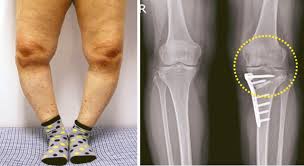

2.2 O자형 다리와 관절염

O자형 다리(내반슬)는 무릎 관절의 내측(안쪽)에 더 많은 부담을 주는 형태로, 이로 인해 내측 연골이 빠르게 닳고 관절염이 심화될 가능성이 크다. 연구에 따르면 O자형 다리를 가진 사람은 정상적인 정렬을 가진 사람보다 무릎 관절염 발병률이 높으며, 관절염이 진행됨에 따라 다리의 변형이 더욱 심해지는 경향을 보인다. 이는 관절염으로 인한 연골 손실이 무릎의 특정 부위에서 더욱 집중적으로 발생하기 때문이다.